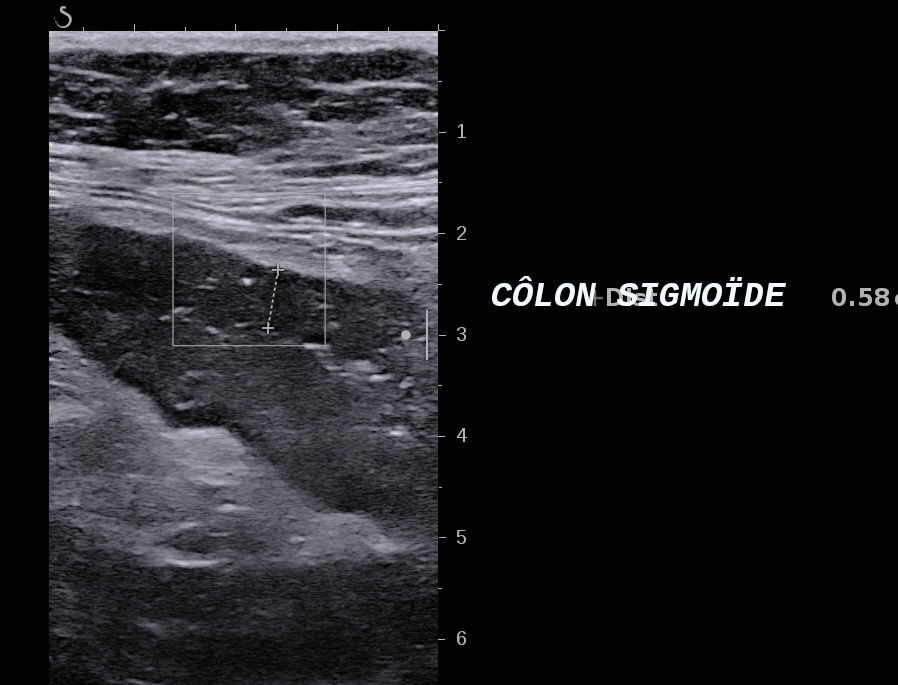

Echographie: colite gauche 8 mm perte de la stratification et ulcère

Là encore la paroi est très hypoéchogène, la structure en couches est par endroit totalement absente, ulcérations en surface, infiltration de la graisse, doppler intense, petites adénopathies périphériques.

Le rectum est bien vu avec la sonde basse fréquence la paroi atteint 10 mm à ce niveau.

Le score de Milan MUC est de (10 x1,4+2) = 16